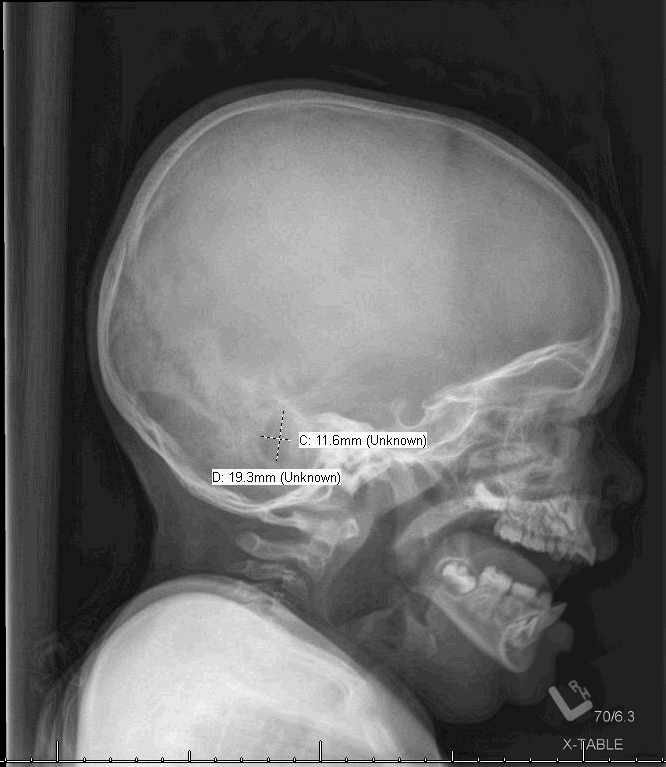

A 13-year-old otherwise healthy girl presented to the emergency department with a 3-week history of progressive swelling of the right side of her neck and underneath the right side of her tongue.

02/09/2021